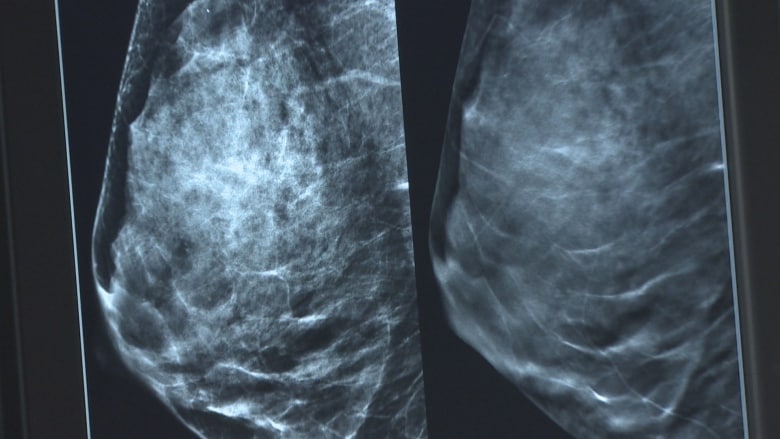

多久检查一次?

Ryan Woods 补充说,非移民妇女的检查率 51.2%,仍然远远低于BC癌症协会的目标 – 70%。

BC 省癌症协会表示,八分之一的女性会在一生中的某个阶段患上乳腺癌,因此应该定期进行检查。

该机构称,BC省为 40 至 74 岁的女性提供免费的乳房 X 光检查,并不需要医生的处方。

对于母亲或姐妹患有乳腺癌的妇女来说,她们患乳腺癌的可能性是其他人的的两倍之多,因此每年都要进行乳房 X 光检查。

对于那些年龄 在50 到 74 岁之间,没有乳腺癌家族史的人,BC 省癌症协会建议每两年进行一次乳房 X 光检查。

75岁及以上的女性,应该每两到三年进行一次检查。

预约乳腺 X 光检查,请给 BC 癌症协会 (B.C. Cancer’s screening programs?)的客服中心打电话:1-800-663-9203